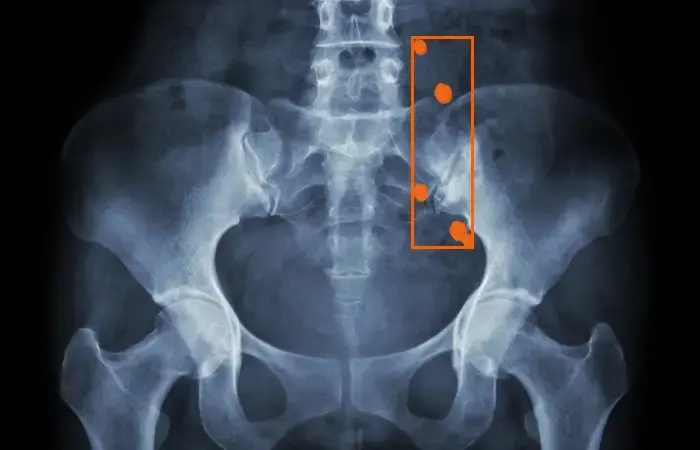

Bounding Boxes for AI in Kidney Stone

Optimizing AI training data through bounding boxes for improving the diagnostic accuracy of kidney stones, determining stone composition, and predicting outcomes of surgical procedures.